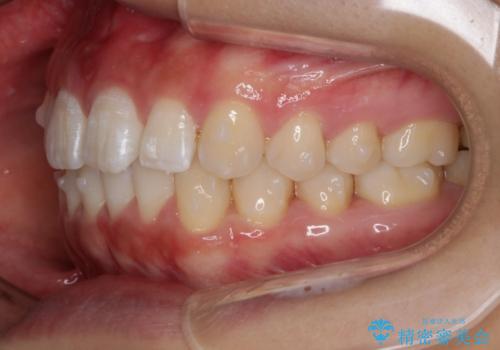

インビザライン矯正 前歯のすきっ歯を治したい

- 上顎の前歯のすきっ歯を治したいとのことで来院されました。

前歯の隙間を閉じる矯正治療の場合、インビザライン適用症例のためインビザラインによる治療をご提案しました。

後戻り防止のため、上唇小帯切除も併用しています。

上唇と歯ぐきを結ぶひも(上唇小帯)が長いと、前歯に隙間が空いてしまうことがあります。今回は隙間を確実に閉じる目的、また矯正後に再び隙間が空かないように、上唇小帯の切除も行っています。